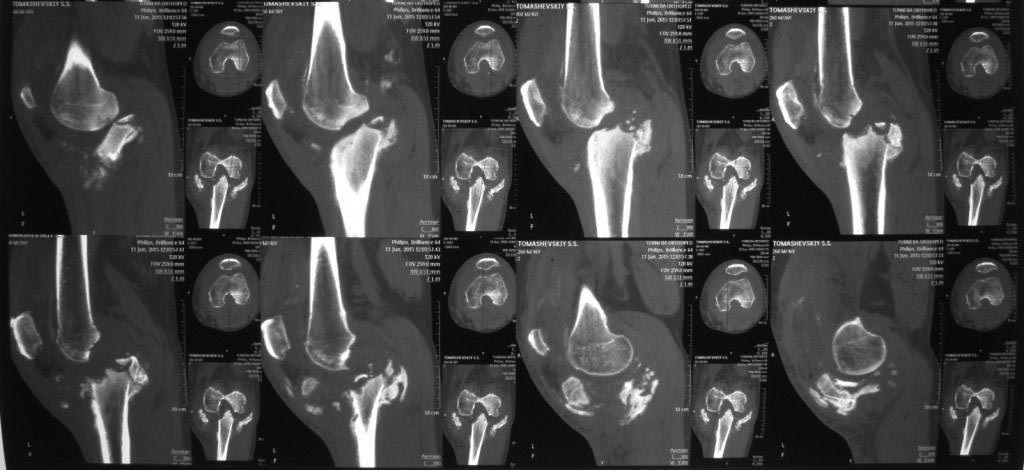

[Ortho] КТ сложного перелома TIBIA

Пациент выполнил КТ коленного сустава. У кого как-то изменилось мнение

про тактику, пожалуйста, напишите. Спасибо

Имя     : IMG_7612.JPG

Размер  : 96980 байтов